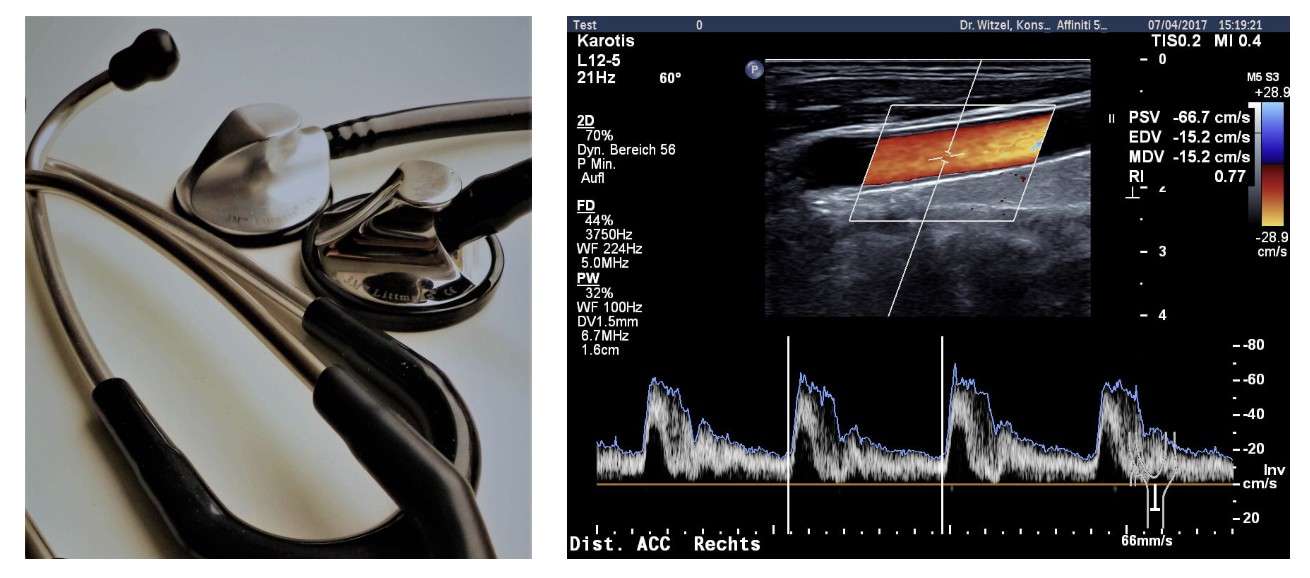

Kardiologie

Unsere Praxis bietet Ihnen eine umfassende fachkardiologische Untersuchung und Betreuung auf Selbstzahlerbasis an. Eine individuelle Behandlung ist uns dabei sehr wichtig.